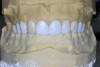

Figure 1  An example of teeth misaligned in the ridge. Orthodontic movement would be necessary to establish proper anterior guidance.

Figure 1

For canine guidance to be achieved, the canine teeth themselves must be in a position to function. Instability causes wear, and as this wear progresses, teeth loose their natural contour. Teeth may also not be in the proper position within the alveolar ridge to allow proper contact in canine guidance (Figure 1 and Figure 2). In these cases, Dr. Dawson describes five choices for correcting occlusal disharmonies.10 They are: